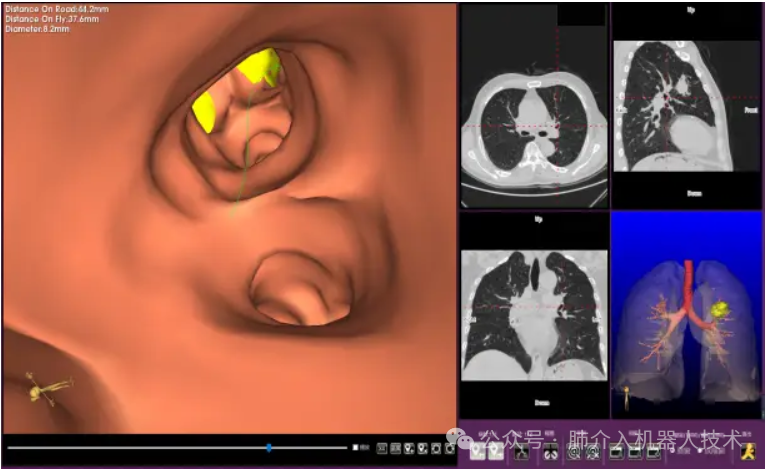

03、奧泰康助力肺部穿刺手術(shù)導(dǎo)航系統(tǒng)獲證

2024年1月31日,經(jīng)國家藥品監(jiān)督管理局公示,蘇州朗開醫(yī)療技術(shù)有限公司自主研發(fā)的肺部穿刺手術(shù)導(dǎo)航系統(tǒng)(國械注準(zhǔn)20243010222)獲得NMPA批準(zhǔn)上市,奧泰康助力本項目注冊申報服務(wù),系2024年奧泰康助力獲得的首張三類醫(yī)療器械注冊證。